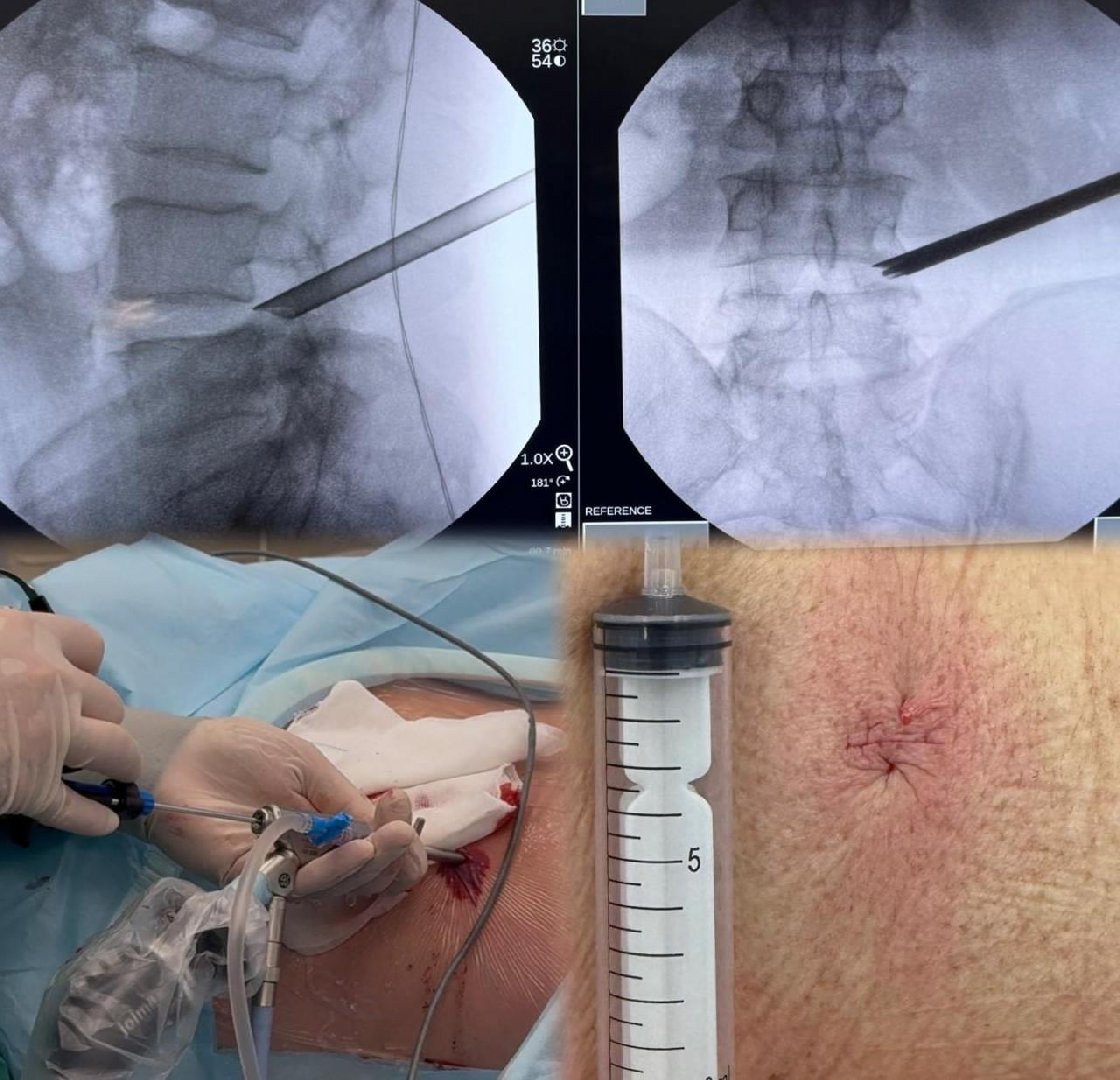

Однако появилось современное решение – малотравматичное эндоскопическое удаление грыжи через прокол около пяти миллиметров. Операцию выполняют с применением высокотехнологичного эндоскопического оборудования, когда нейрохирург видит операционное поле на экране с многократным увеличением.

«Это позволяет удалить грыжу без травм, сохранив окружающие структуры спинного мозга и позвоночника. В нейрохирургическом центре МОНИКИ малотравматичные эндоскопические операции на позвоночнике проводят опытные специалисты, владеющие современными технологиями. Индивидуальный подход к каждому пациенту обеспечивает безопасность и эффективность вмешательства, быстрое восстановление», – пояснил руководитель отделения нейрохирургии МОНИКИ Реваз Джинджихадзе.Среди преимуществ нового метода лечения – то, что вместо большого разреза делают лишь маленький прокол. Это даёт хороший косметический результат, сохраняет анатомию позвоночника и позволяет пациенту быстрее вернуться к повседневной жизни.